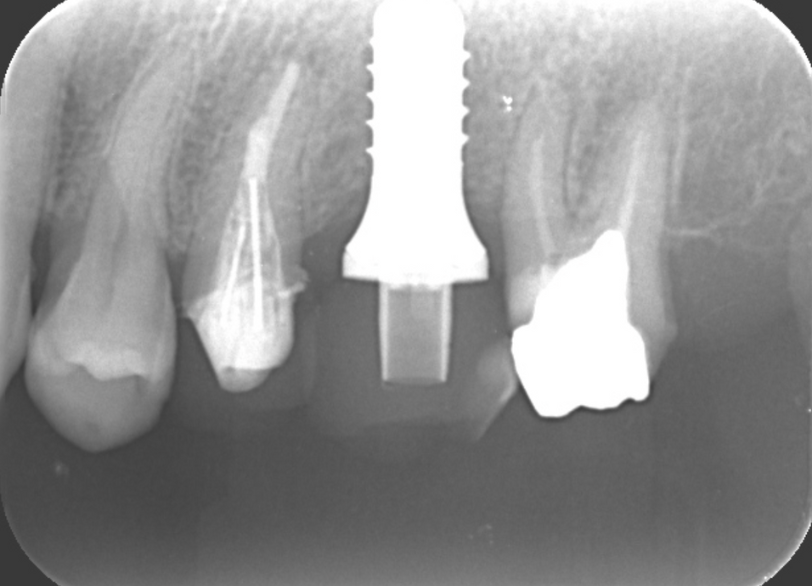

③インプラントを埋入し仮歯装着

③インプラント上部構造装着

(かみ合わせの歯が義歯の為問題がないと考えた)

| 診断 | ①下顎両側臼歯欠損 ②上顎左側5根尖性歯周炎 ③上顎左側6欠損 ④上顎右側4歯根破折 ⑤上顎右側567欠損 ⑥上顎左側7う蝕 ⑦上顎右側7う蝕 |

| 処置内容 (または主訴) | ①義歯 ②顕微鏡を用いた感染根管治療 ③インプラント治療 ④抜歯→骨造成→インプラント ⑤インプラント治療 ⑥セラミックによる被せ物の修復 ⑦セラミックによる被せ物の修復 |